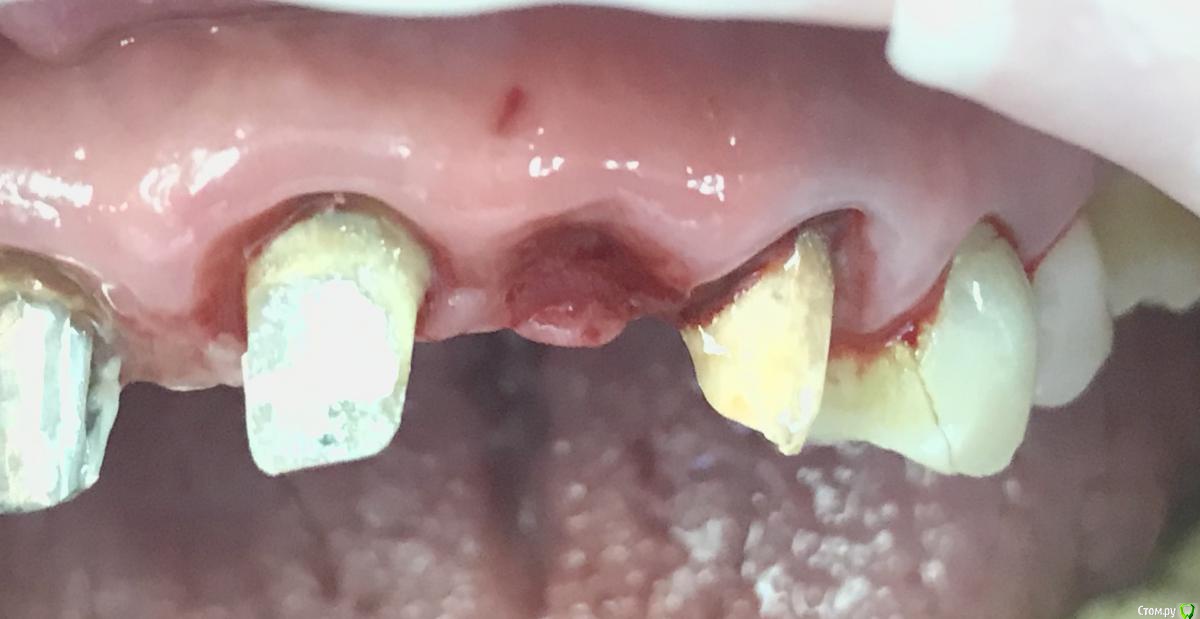

колесников Опубликовано 10 мая, 2019 Поделиться Опубликовано 10 мая, 2019 Удаление с консервацией под мост,закрыто быстрымноймаером. Вид через 3 недели . Удаление повязки,под ней не созревший гранулят,замена на овоид. Следующий визит через месяц,посмотрим будет ли стабилен десневой контур. 3 Ссылка на комментарий

andrey75 Опубликовано 27 июня, 2019 Поделиться Опубликовано 27 июня, 2019 Удалял сразу ставил первичой стабильности под формик нет, вестибулярная кортикалка пергамент. Закрыл шайбами. думаю будет отличный профиль для ортопеда. 2 Ссылка на комментарий